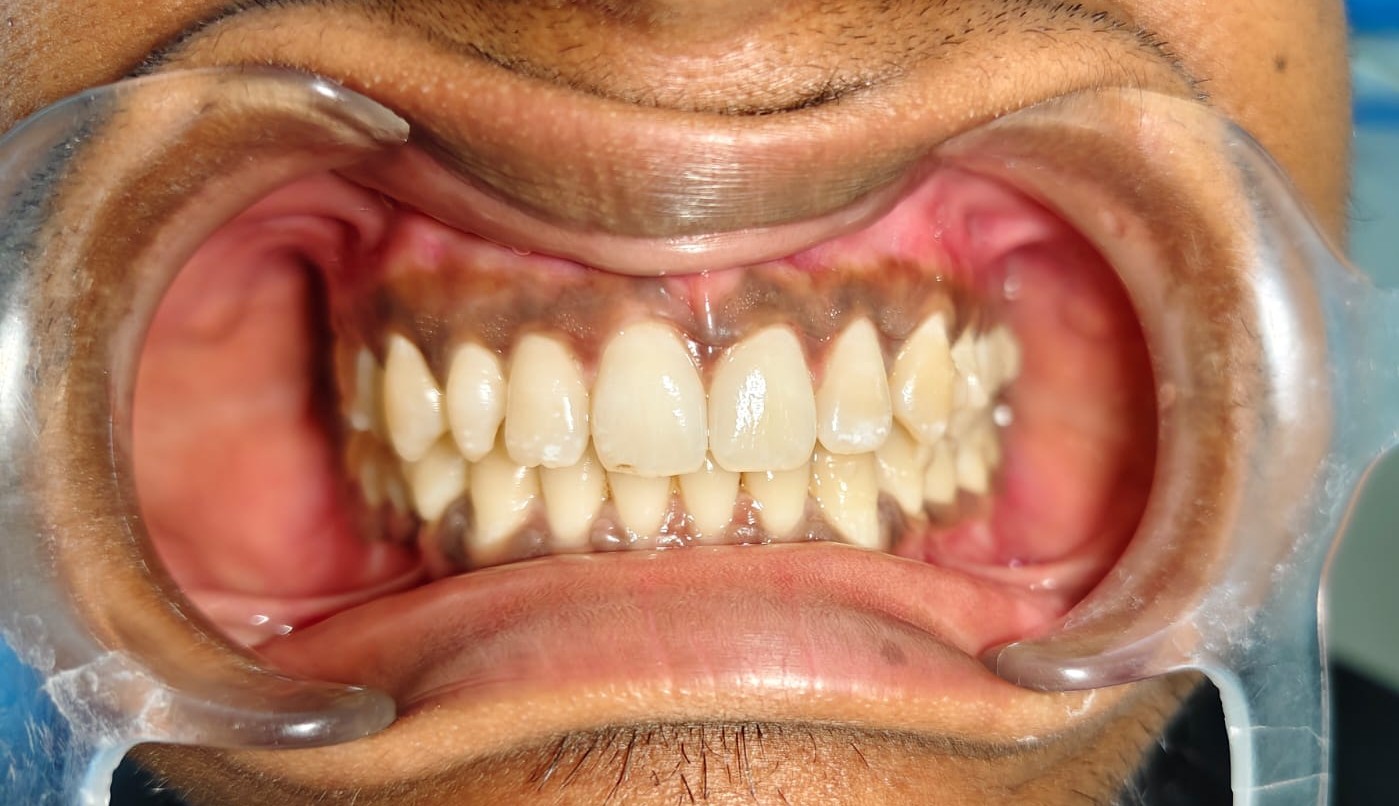

After/Before

See stunning smile transformation before and after

Before After